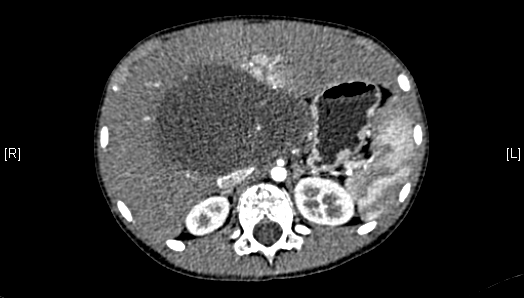

术前CT检查:

静脉期

腹部超声示:肝内包块。腹部CT:肝脏占位,血管瘤?上腹部增强CT:肝左内叶-右前叶交界区、尾叶囊实性团块影,考虑肿瘤(胆管囊腺瘤?间叶性错构瘤?)